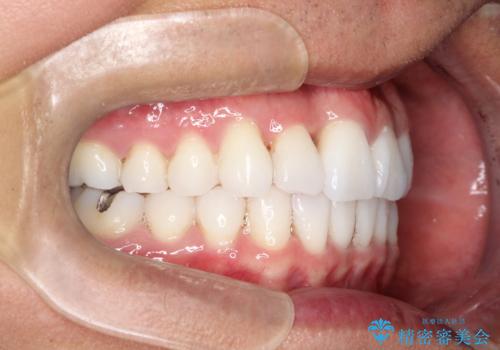

右上の前から2番目の歯が引っ込んで、下の前歯にはガタガタがありました。

上下の歯と歯の間を少量ずつ削りスペースを作り、インビザラインにて並べる計画としました。

目立たずに矯正治療を終えることができたことに満足していただけました。